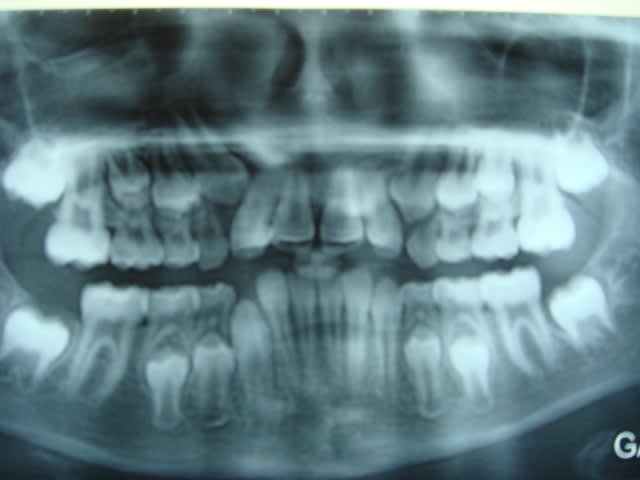

petit fille (10 ans)qui n'a soit disant jamais sucé son pouce (j'en doute) vu la poussée du prémaxillaire) ou magnifique travail de la langue

le reste (bien que l’on ait pas de moulage) peut réserver encore des surprises

succion de la lévre inférieure+plan terminal qui nous oriente vers une future classe II+manque de place pour l'éruption des canines supérieures(signe de Quintero),j'aurais proposé un lip bumper fixé sur les molaires supérieures.